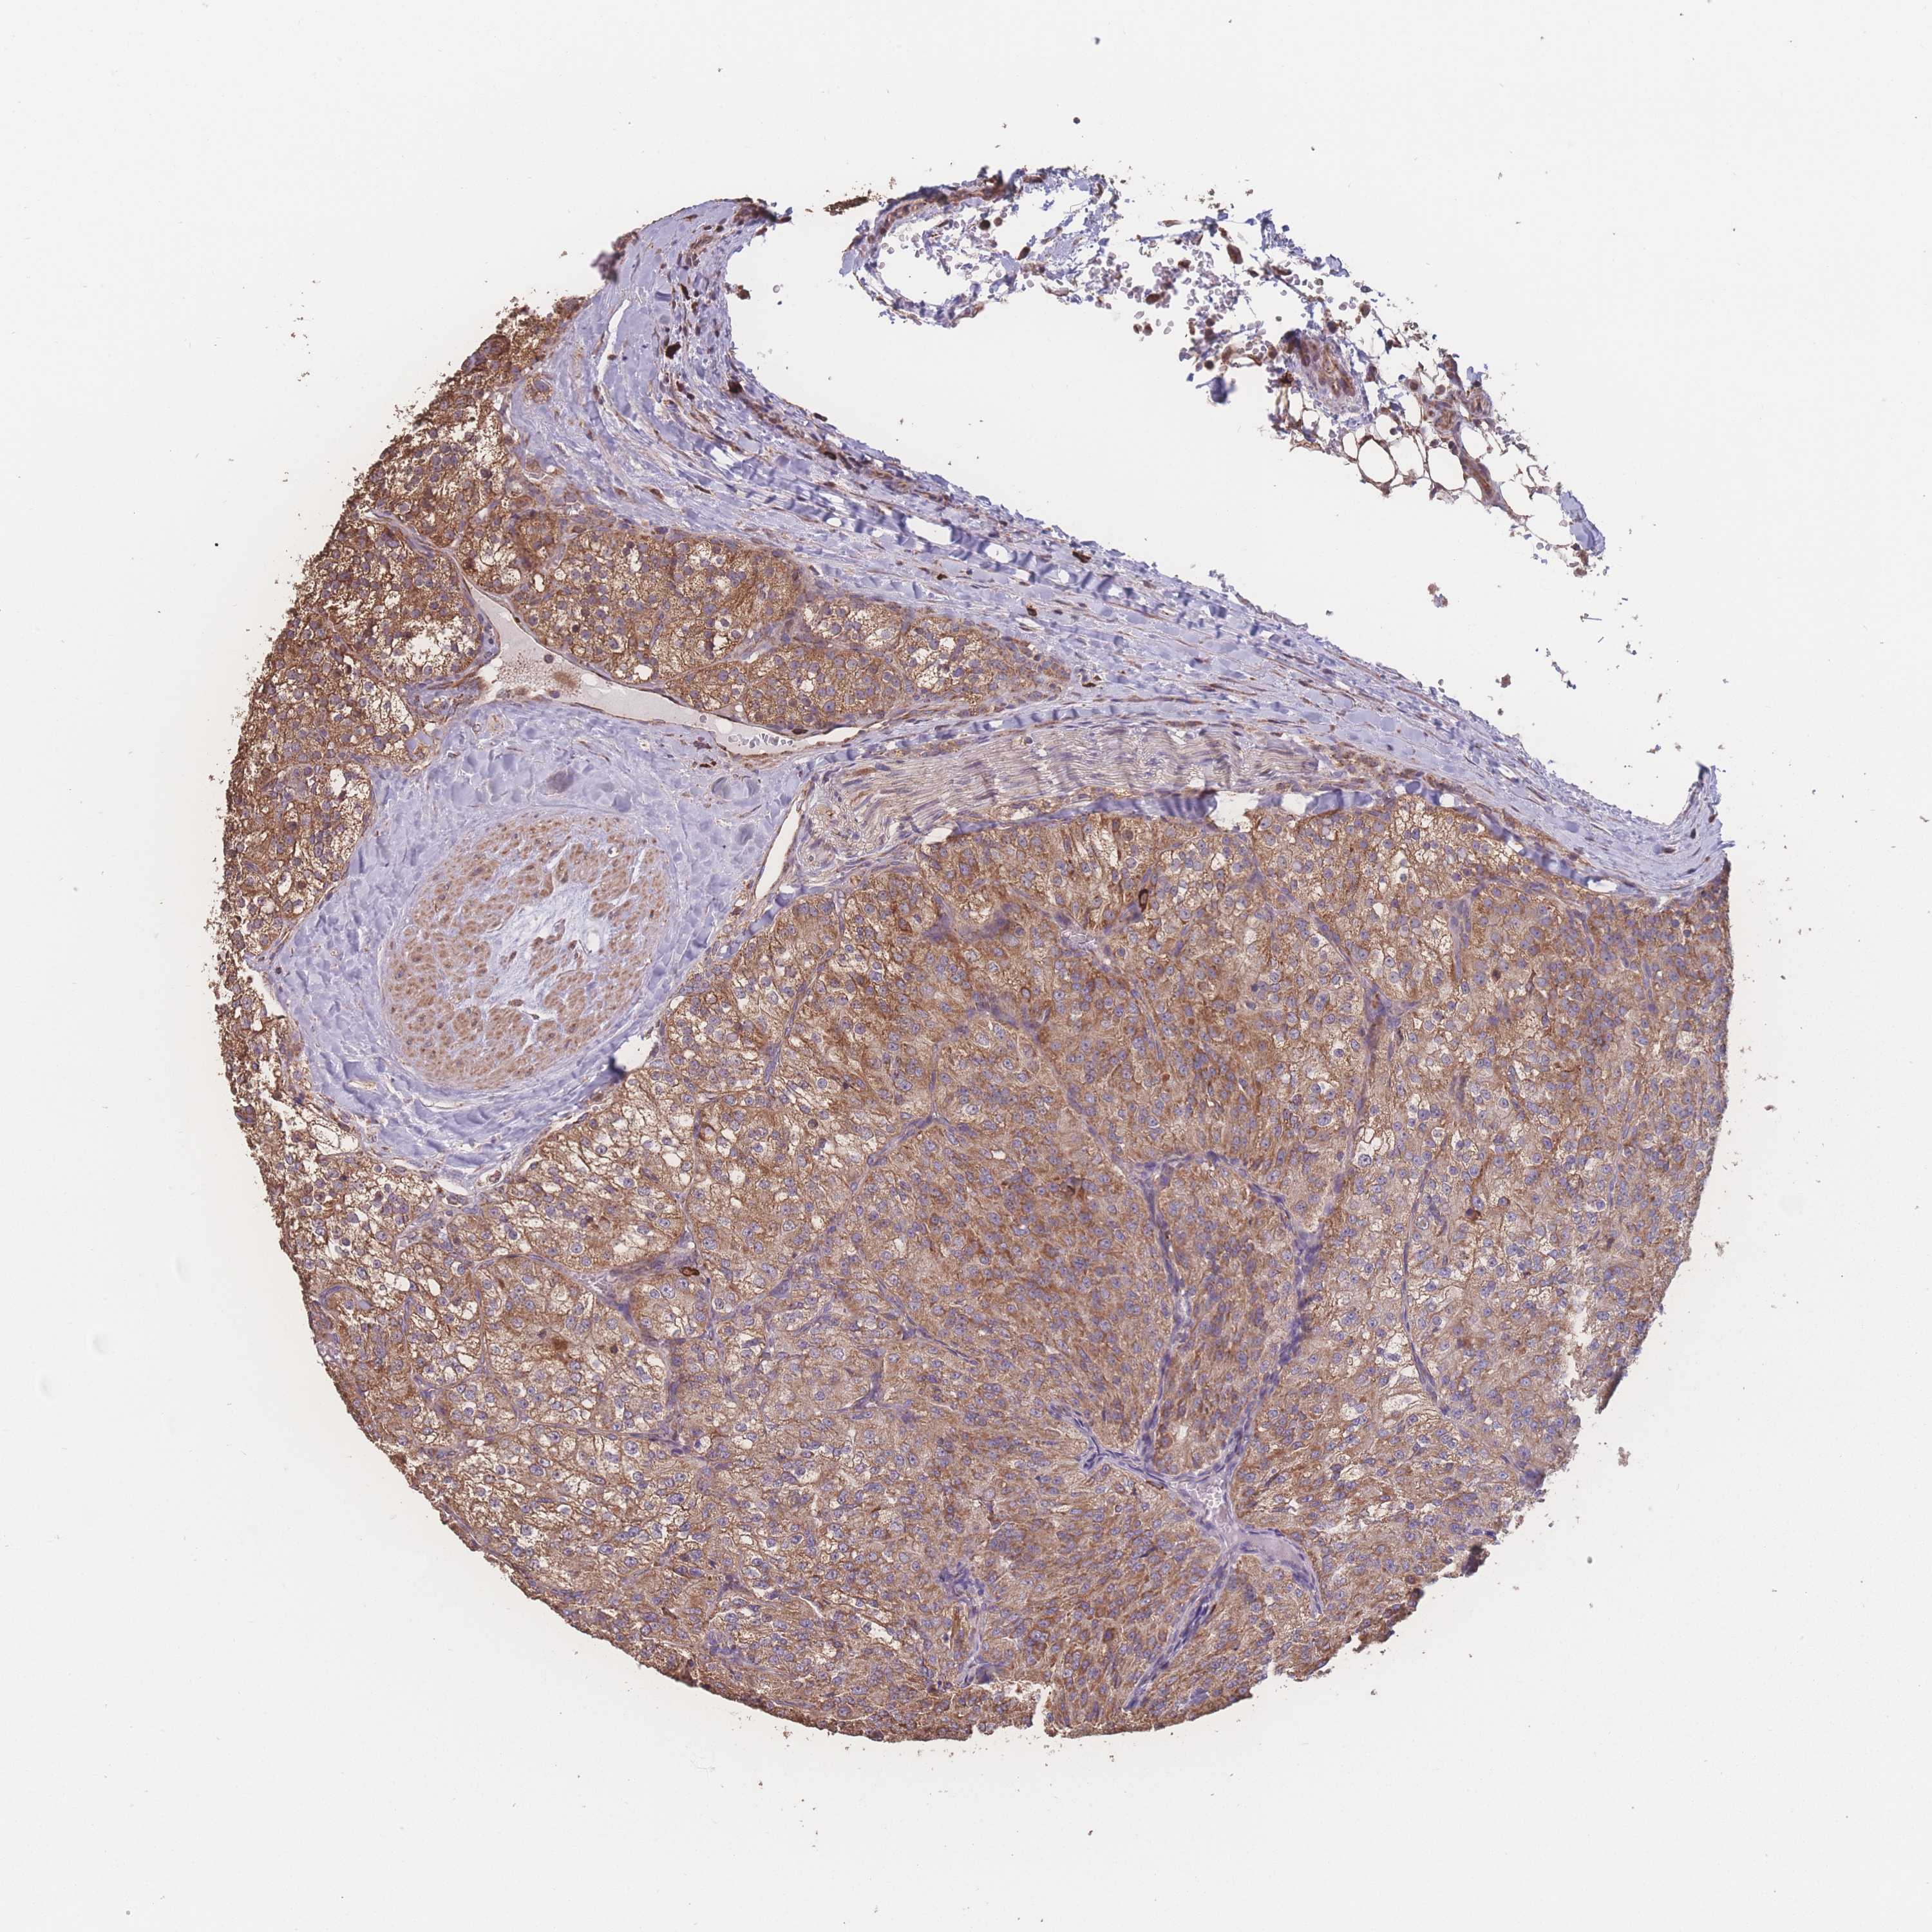

KIDNEY RENAL CLEAR CELL CARCINOMA (VALIDATION) - Interactive survival scatter ploti

The Survival Scatter plot shows the clinical status (i.e. dead or alive) for all individuals in the patient cohort, based on the same data that underlies the corresponding Kaplan-Meier plots. Patients that are alive at last time for follow-up are shown in blue and patients who have died during the study are shown in red.

The x-axis shows the expression levels (FPKM) of the investigated gene in the tumor tissue at the time of diagnosis. The y-axis shows the follow-up time after diagnosis (years). Both axes are complimented with kernel density curves demonstrating the data density over the axes. The top density plot shows the expression levels (FPKM) distribution among dead (red) and alive patients (blue). The right density plot shows the data density of the survived years of dead patients with high and low expression levels respectively, stratified using the cutoff indicated by the vertical dashed line through the Survival Scatter plot. This cutoff is automatically defined based on the FPKM cutoff that minimizes the p-score. The cutoff can be changed by dragging the vertical line or by entering a cutoff value in the square labeled "Current cut-off".

Under the Survival Scatter plot the p-score landscape (black curve; left axis) is shown together with dead median separation (red curve; right axis). Dead median separation is the difference in median mRNA expression between patients who have died with high and low expression, respectively. It is calculated as follows: median FPKM expression of dead patients with high expression - median FPKM expression of dead patients with low expression. This is intended to aid the user in visually exploring custom cutoffs and the associated p-scores and dead median separation.

Individual patient data is displayed and can be filtered by clicking on one or more of the category buttons on the top of the page. Categories describing expression level and patient information include: high, low, alive, dead, female, male and tumor stages. The scale of the x-axis can be toggled between linear and log-scale by clicking on the "x log" button. Mouse-over function shows TCGA ID, patient information and mRNA expression (FPKM) for each patient.

& Survival analysisi

Kaplan-Meier plots summarize results from analysis of correlation between mRNA expression level and patient survival. Patients were divided based on level of expression into one of the two groups "low" (under cut off) or "high" (over cut off). X-axis shows time for survival (years) and y-axis shows the probability of survival, where 1.0 corresponds to 100 percent.

SGSM3 is not prognostic in Kidney Renal Clear Cell Carcinoma (validation)

Best expression cut offi

Based on the FPKM value of each gene, patients were classified into two groups and association between prognosis (survival) and gene expression (FPKM) was examined. The best expression cut-off refers the FPKM value that yields maximal difference with regard to survival between the two groups at the lowest log-rank P-value. Best expression cut-off was selected based on survival analysis .

When clicking on this number, the vertical dashed line indicating cut-off, the interactive survival plot, and the Kaplan-Meier curve will be adjusted to show results based on the best expression cut-off.

: 29.9

P scorei

Log-rank P value for Kaplan-Meier plot showing results from analysis of correlation between mRNA expression level and patient survival.

N/A

TCGA RNA samplesi

RNA-seq data is reported as average FPKM (number Fragments Per Kilobase of exon per Million reads), generated by the The Cancer Genome Atlas (TCGA) .

Normal distribution across the dataset is visualized with box plots, shown as median and 25th and 75th percentiles. Points are displayed as outliers if they are above or below 1.5 times the interquartile range. FPKM values of the individual samples are presented next to the box plot.

Average pTPM 27.1

Number of samples 100